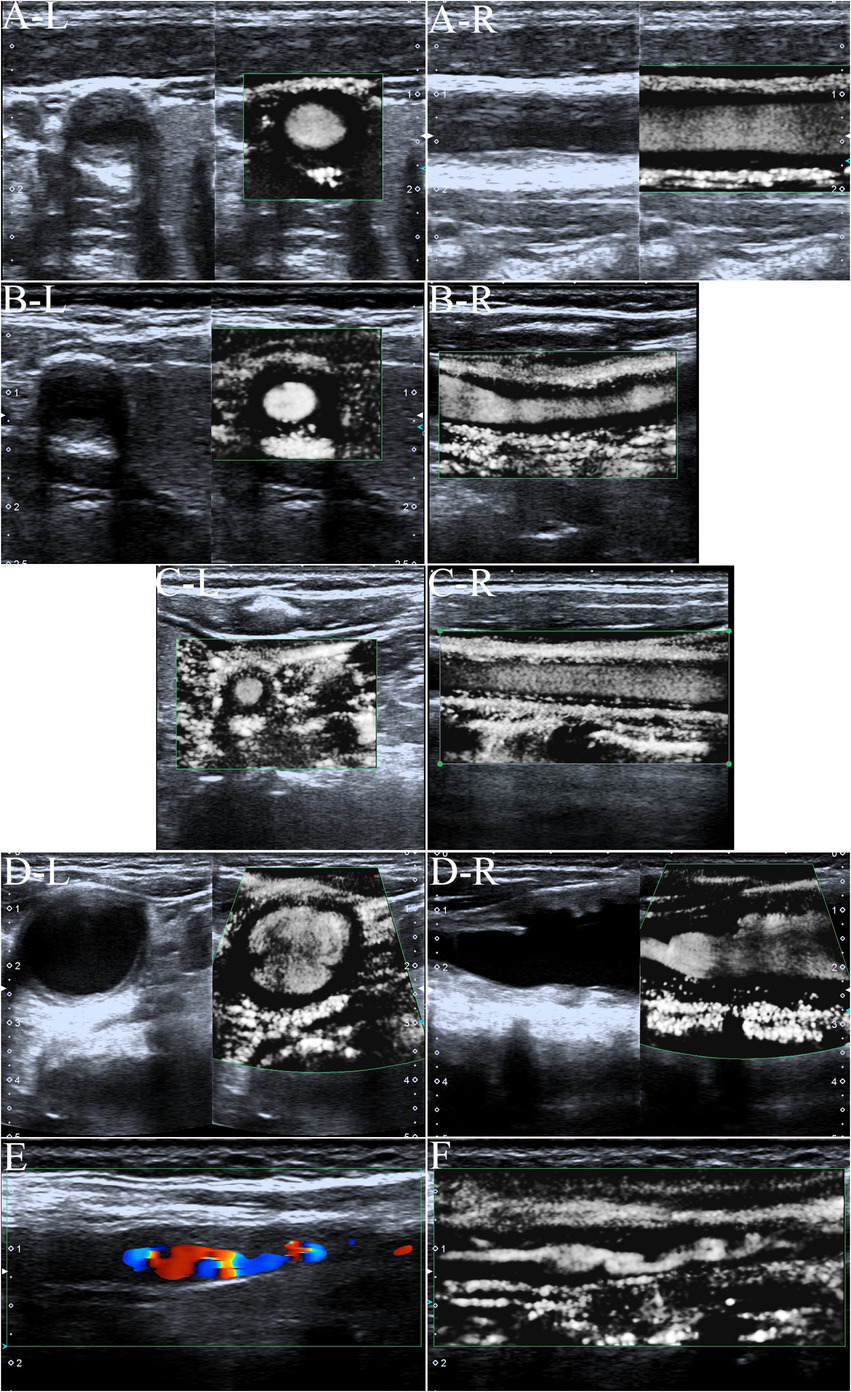

Imaging characteristics of carotid ultrasound

Artery walls with concentric thickening, narrowing of the vascular diameter, and stenosis or occlusion of the lumen could be observed by carotid ultrasound (Figures 1, 2). In addition, carotid arterial aneurysms were readily observed (Figure 1D). SMI was able to display low blood flow signals in the lumen (Figures 1E,F, 2C,D) and concentric thickened walls of affected carotids (Figures 1B–D) that color Doppler could not. SMI can observe the collateral flow (the meandering, twisted, narrow blood flow signals) in the thickened vessel walls (Figures 2E,F). SMI improved image quality, enhanced the vessel wall and lumen, and gave a better definition of the borders of the vascular lesion (Figures 2A,B). Furthermore, we observed moving bright spots and linear flow within the vascular lesions that were principally visualized on the adventitial side of the vessels (Figure 1C), and we believe these signals represent neovessels of the neovascularization that could be visualized by SMI, only 55% could be visualized using color Doppler.

Figure 1

The superb microvascular imaging (SMI) of the carotid artery. (A) SMI G0, no visible short lines, dots, or short sticks of medium-high echogenic within the wall of the carotid artery (Left: Transverse section, Right: Longitudinal section). The asterisk marks the bloodstream in the carotid artery canal. The arrow shows the thickened wall of the carotid artery. (B) SMI G1, moderate visible short lines, dots, or short sticks of medium-high echogenic within the wall. The arrow shows neovessels in the thickened wall of the carotid artery (Left: Transverse section, right: Longitudinal section). (C) SMI G2, extensive visible short lines, dots, or short sticks of medium-high echogenic within the wall of the carotid artery. The arrow shows neovessels in the thickened wall of the carotid artery (Left: Transverse section, right: Longitudinal section). (D) Carotid lumen expansion and aneurysm formation (Left: Transverse section, Right: Longitudinal section). The asterisk marks the bloodstream in the carotid artery canal. The arrow shows neovessels in the thickened wall of the carotid artery aneurysm. (E) Color Doppler flow imaging showing carotid stenosis and segmental occlusion. (F) In contrast with (E), SMI was able to clearly show low blood flow signals in the same carotid stenosis and segmental occlusion cavities.